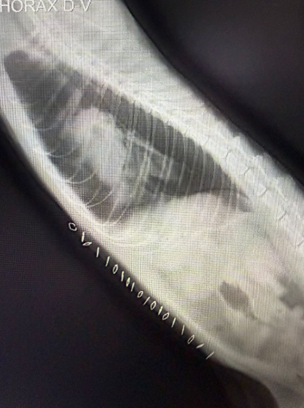

圖四| 手術完成後影像,顯示個案已接受橫隔膜修補及相關處理。